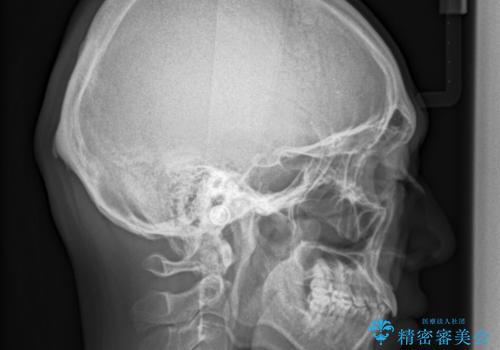

- 以前、上下左右4本抜いてワイヤー矯正をしていた方で、後戻りで下の前歯のガタガタを気にして来院されました。

マウスピース矯正にて、下の歯はIPR(歯と歯の間を削る)を入れることでガタガタの改善、咬み合わせの深さも改善をはかる治療計画をたてました。